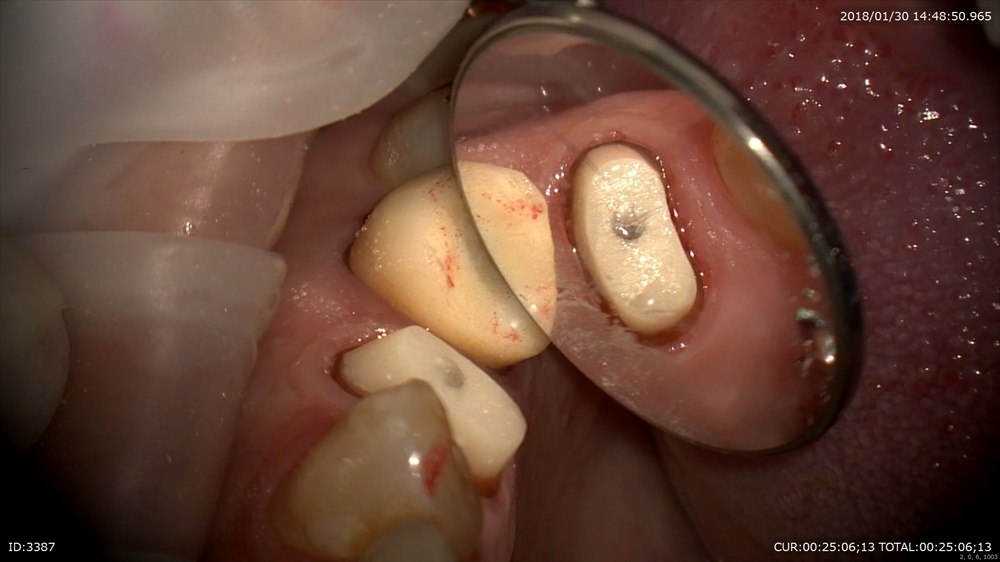

精密根管治療が終わると土台を立てます。

丁寧に削ります。

ここから仮歯を作りフィット

ガイドや形を与えます。